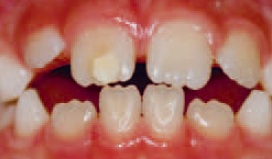

Den økologiske plakhypotese med sin tynde biofilm, er medvirkende årsag til, at der stadig er mange med huller i tænderne. I Tandlægebladet nr. 3/2013 side 198.